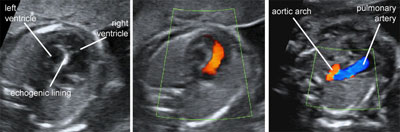

Hypoplastic left heart syndrome

Legend:Hypoplastic left heart syndrome: there is a small left ventricle with an internal echogenic lining suggestive of endocardial fibroelastosis, there is no flow across the mitral valve and the aortic arch is perfused in a retrograde manner